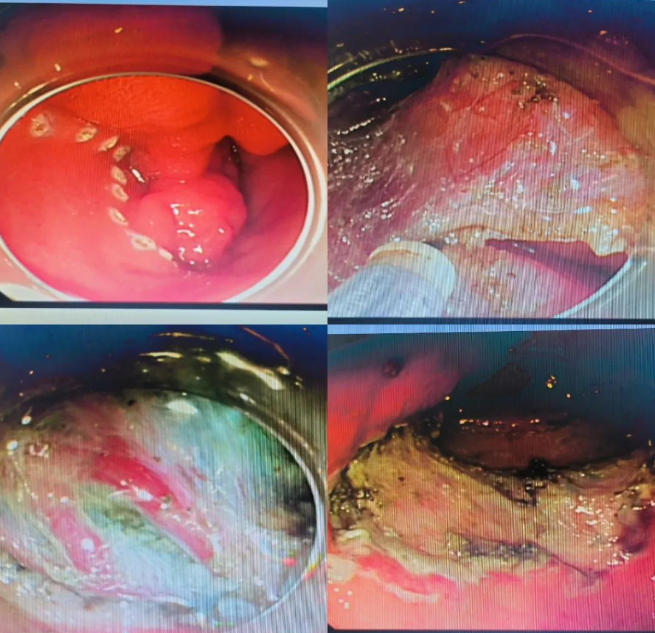

检查结果证实了大家的推测,患者胃镜提示:置底、体见弥漫性大小直径约0.5-2.0cm广基隆起,表面粗糙,边界清楚。胃窦见一大小约5x13cm隆起,呈分叶状.表面粘膜粗糙,边界尚清楚。肠镜见全结肠弥漫性大小约0.5-1.0cm 广基隆起。胃窦较大病变予取材送检,病检回报示:错构瘤性息肉。患者胃窦巨大病变,若不及时切除癌变风险极大,但患者年纪较轻,如果进行传统外科胃大部分切除术对患者后续生活质量影响较大。经讨论后,为患者进行胃镜下胃窦病变粘膜下剥离术为最佳手术方式,但是因患者病变巨大,手术难度大,剥离过程中出血及穿孔风险极大,这也为手术增加了不少难度。与此同时患者强烈要求就在本院进行手术治疗。

本着信任和解决难题的初衷,经过全科病历讨论后为患者制定了详细的手术方案及术前准备,历时六个小时,终于成功为患者完成了内镜下胃窦巨大肿物ESD 术,瘤体完整剥离,创面无残留,术中出血約50m1,离体标本大小5. 0X13CM。内镜诊断。术后病检符合P-J息肉诊断。